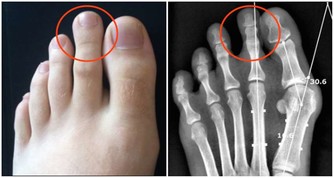

而且腳趾、膝蓋、肩膀和手指等部位,屬於運動較多的關節區,

因為脂肪、血管皆相對較少,熱度容易散失。